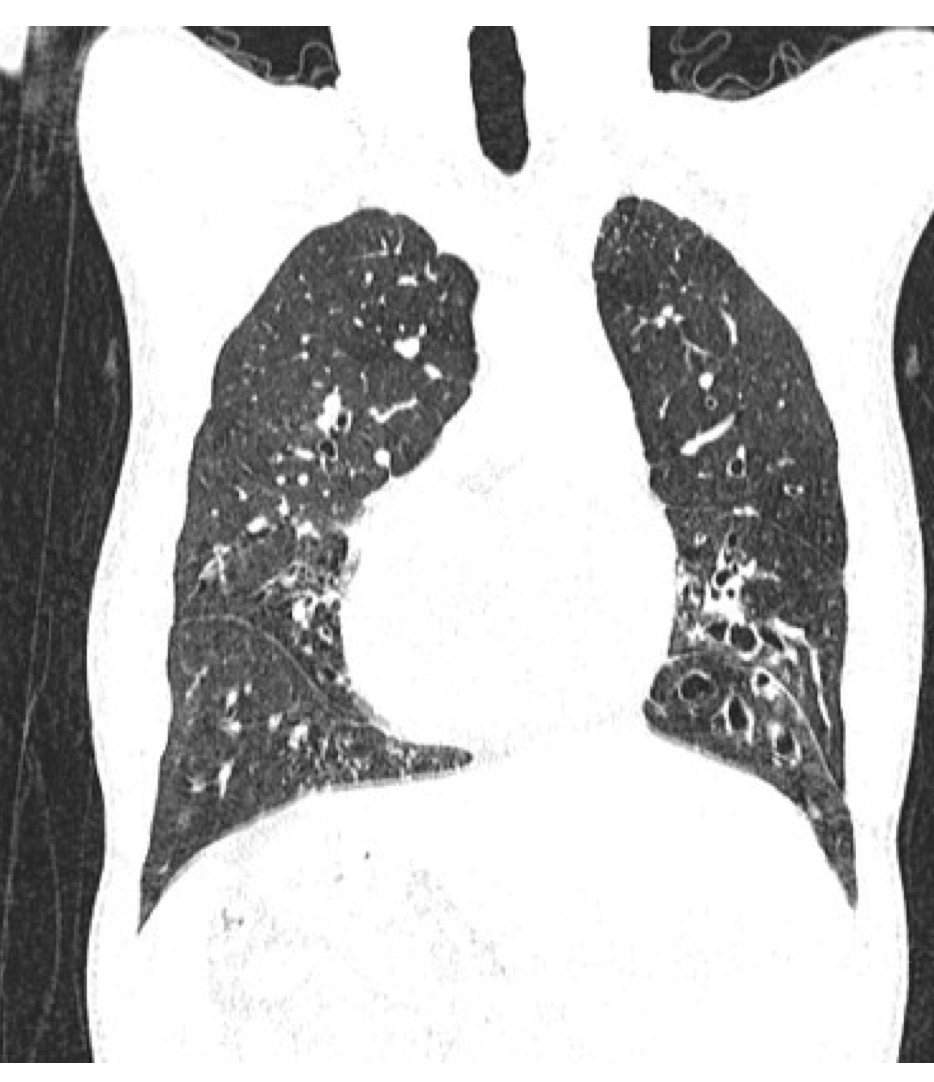

Quais são as manifestações clinicas respiratórias da fibrose cística? O que esperar de QC? Raio X/TC?

A

Secreções espessas geram comprometimento do clearance muco ciliar e favorece infecções

• pólipos nasais

• bronquiectasias

• baqueteamento digital

RAIO X e TC: bronquiectasias e plugs mucosos